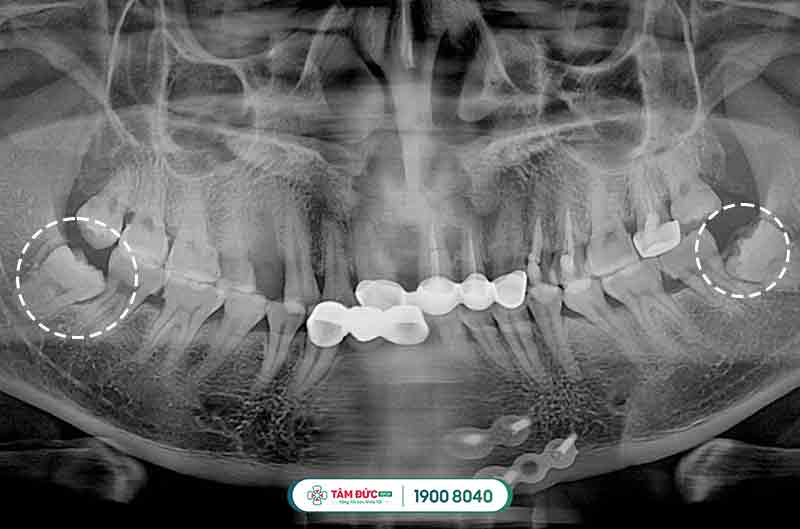

Đối với các trường hợp mọc răng khôn bị thiếu chỗ vì lúc này xương hàm đã ngừng tăng trưởng và phát triển, chịu tác động bởi quá trình ăn uống hàng ngày, khiến răng khôn bị mọc ngầm dưới nướu, mọc lệch đâm vào má, vào răng bên cạnh gây nên tình trạng đau răng khôn dữ dội, khó chịu và ảnh hưởng đến cấu trúc hàm mặt, sức khỏe răng miệng.

Răng khôn mọc ngầm thường có hiểu hiện làm nướu sưng tấy, viêm đỏ, khó há miệng. Vì xương hàm không có đủ vị trí nên nó sẽ đâm sang răng bên cạnh, nó sẽ làm chiếc răng khỏe mạnh kế bên dần bị tiêu hủy, lung lay có thể dẫn đến sâu, nặng hơn nó sẽ khiến chiếc răng này bị xô đẩy chèn ép và rụng đi gây mất răng. Răng khôn mọc lệch, ngầm thường gây ra những cơn đau răng khôn âm ỉ kéo dài trong khoản 2 tới 3 ngày.

Còn những cơn đau răng khôn mọc lệch, mọc ngầm sẽ lặp đi lặp lại nhiều lần trong suốt quá trình răng khôn mọc, gây ra những biến chứng nguy hiểm, không thể ăn nhai, ảnh hưởng đến học tập, công việc và sinh hoạt hàng ngày. Cần phải đến ngay các trung tâm nha khoa để các bác sĩ thăm khám và tư vấn nên nhổ bỏ hay không.